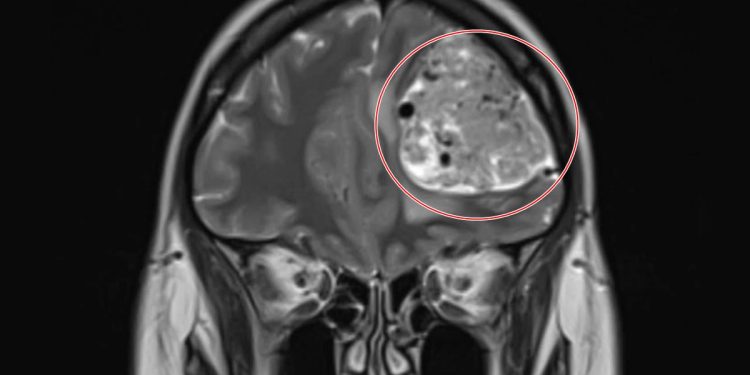

Com dor de cabeça frequente, mulher descobre tumor cerebral de 15 anos

A professora britânica Nikita Sterling conviveu por mais de duas décadas com enxaquecas que acreditava serem apenas incômodos ocasionais. Os episódios começaram aos 18 anos e se mantiveram pouco frequentes durante muitos anos. No começo de abril de 2025, aos 39 anos, ela foi diagnosticada com meningioma de grau 1.

Ao decidir pagar aproximadamente R$ 2,5 mil por uma ressonância magnética particular, a vida da mulher mudou: poucas horas depois, ela recebeu uma ligação pedindo que fosse imediatamente ao hospital, pois os exames revelaram uma grande massa em seu lobo frontal esquerdo.

Nikita lembra do choque ao ver a imagem do tumor e ouvir do médico que se tratava de uma lesão cerebral de grandes proporções.

A recuperação, no entanto, não foi simples: ela enfrentou inchaço no rosto, pontos extensos na cabeça e perda temporária de sensibilidade no couro cabeludo. Ainda assim, poucas semanas depois, recebeu a melhor notícia possível: o tumor era benigno e de crescimento lento. Segundo os médicos, ele provavelmente esteve em evolução por mais de 15 anos.

Foto colorida de uma grande cicatriz na cabeça, após retirada de tumor - MetrópolesNikita Sterling, 39 anos, foi diagnósticada com meningioma de grau 1. tumor benigno de crescimento lento